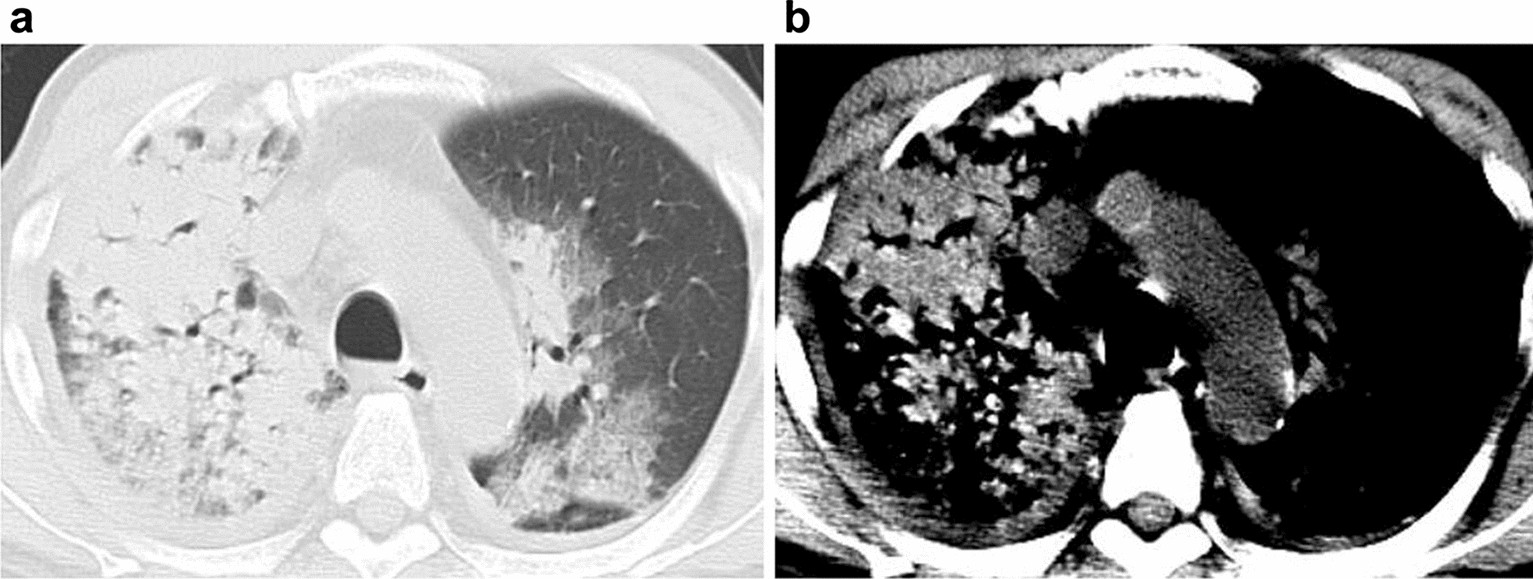

Figure 3

70-year-old man with diffuse alveolar hemorrhage in microscopic polyangiitis. (a) Transaxial CT with a lung window setting showing the consolidations and ground-glass opacities. (b) The hyperdense consolidation sign is seen in the narrow window setting with a mediastinal filter.